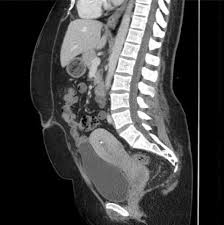

Ct Abdomen Pelvis Sagittal View Prominent Cervix With Mixed Density Download Scientific Diagram

Ct Abdomen Pelvis Sagittal View Prominent Cervix With Mixed Density Download Scientific Diagram from www.researchgate.net